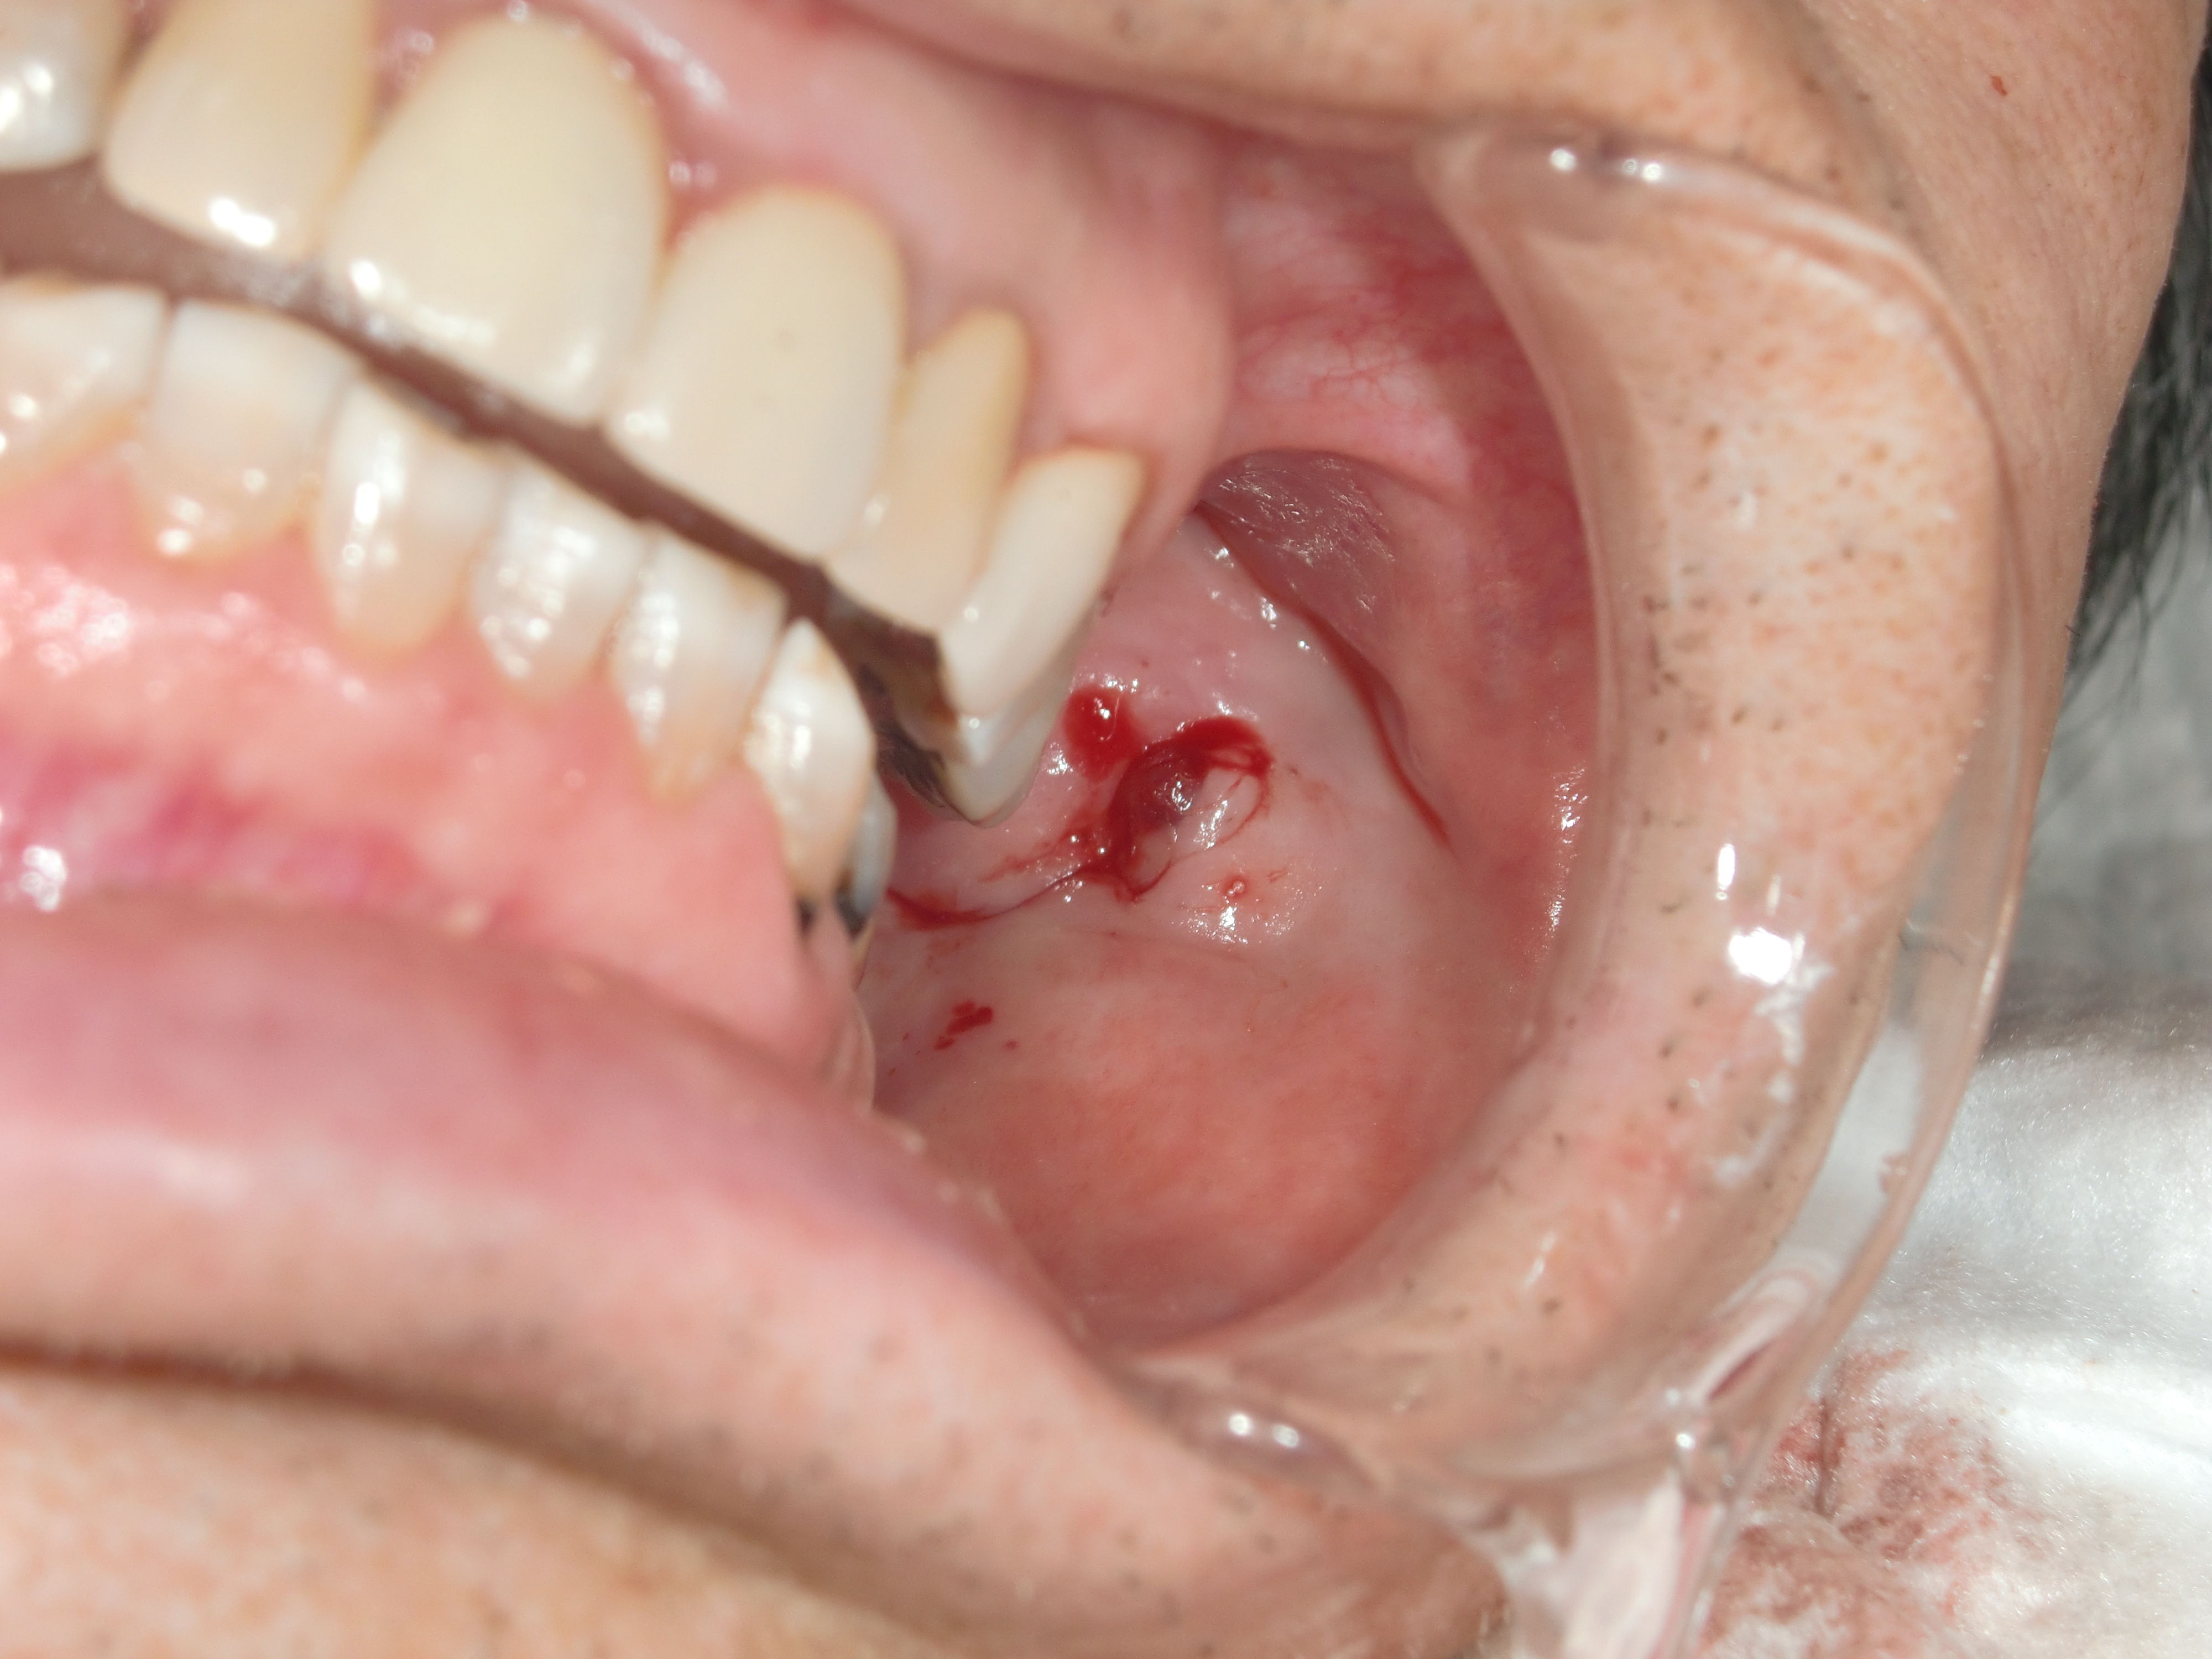

口腔内を確認すると、歯がかけていて、その部分が鋭利になっており、

それが頬を傷つけていたということがわかりました。

傷の部分を縫合し、歯の鋭利になっている部分を丸めるようにすれば

次の日には出血が全くなくなったと連絡がありました。